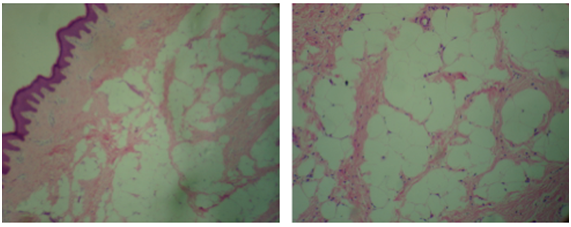

The patient underwent mass resection and clitoridoplasty. Surgical findings reported a dependent lesion in prepubic area, at the level of the suspensory ligament and extending to the tip of the clitoris (Figure 3a). Tunica albuginea and neurovascular bundles were identified and preserved (Figure 3b). Final pathological analysis reported superficial cutaneous lipomatous nevus (Figure 4). The patient was followed in the clinic postoperatively for 10 months with adequate medical progress, without signs or symptoms of recurrence and currently with a normal female genitalia appearance (Figure 5a & 5b).

Figure 4: Haematoxylin and eosin stain, transverse cut of mass showing a lipoma with mature white adipocytes and numerous capillary blood vessels. No immature, atypical adipocytes or mitotic signs.